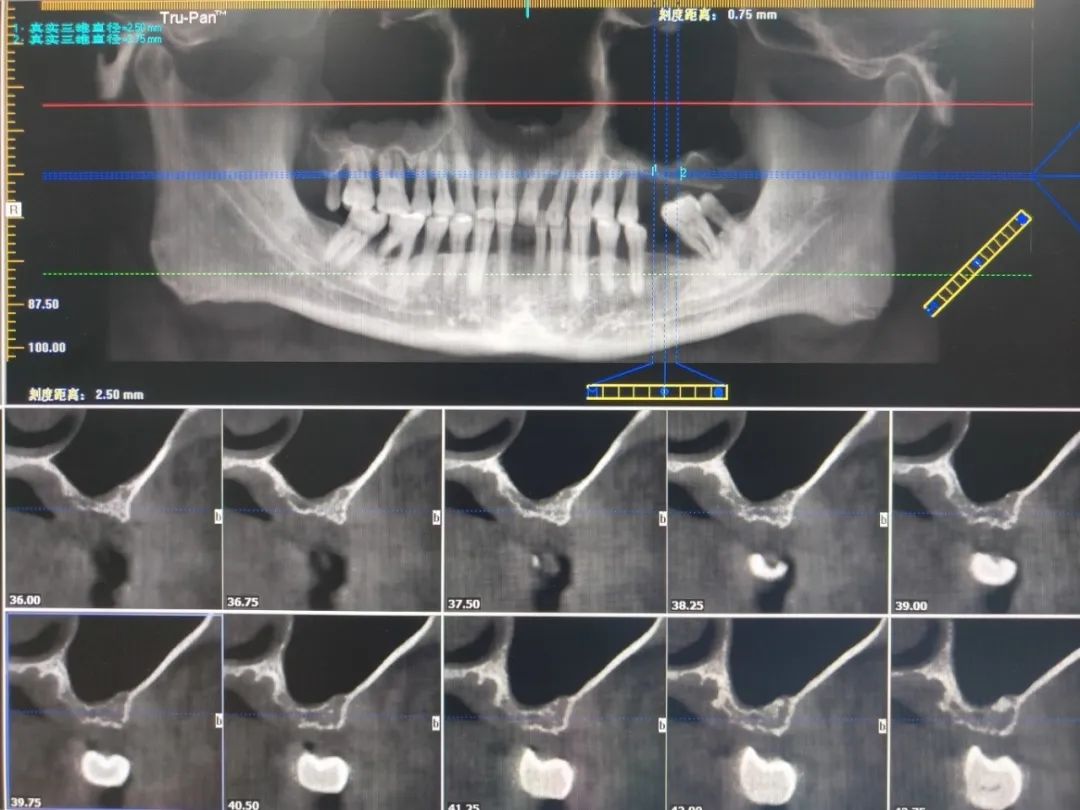

此次手术患者为一名左侧上颌后牙缺失患者,因炎症吸收与长期缺牙导致牙槽骨高度不足(剩余骨高度仅2.50mm—3.75mm),无法直接植入种植体。术前通过锥形束口腔CBCT精准评估上颌窦底形态、骨量及黏膜厚度,最终选择效果较稳定的外提升术式。术中,在心电监护下,通过上颌窦黏膜提升与骨填充,成功将骨高度提升15.50mm—16.50mm,术后影像显示即刻植骨形态良好,窦底黏膜完整无穿孔。